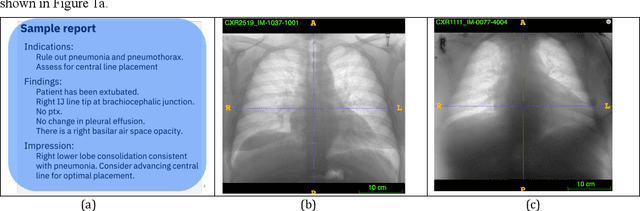

Abstract:Chest radiographs are the most common diagnostic exam in emergency rooms and intensive care units today. Recently, a number of researchers have begun working on large chest X-ray datasets to develop deep learning models for recognition of a handful of coarse finding classes such as opacities, masses and nodules. In this paper, we focus on extracting and learning fine-grained labels for chest X-ray images. Specifically we develop a new method of extracting fine-grained labels from radiology reports by combining vocabulary-driven concept extraction with phrasal grouping in dependency parse trees for association of modifiers with findings. A total of 457 fine-grained labels depicting the largest spectrum of findings to date were selected and sufficiently large datasets acquired to train a new deep learning model designed for fine-grained classification. We show results that indicate a highly accurate label extraction process and a reliable learning of fine-grained labels. The resulting network, to our knowledge, is the first to recognize fine-grained descriptions of findings in images covering over nine modifiers including laterality, location, severity, size and appearance.